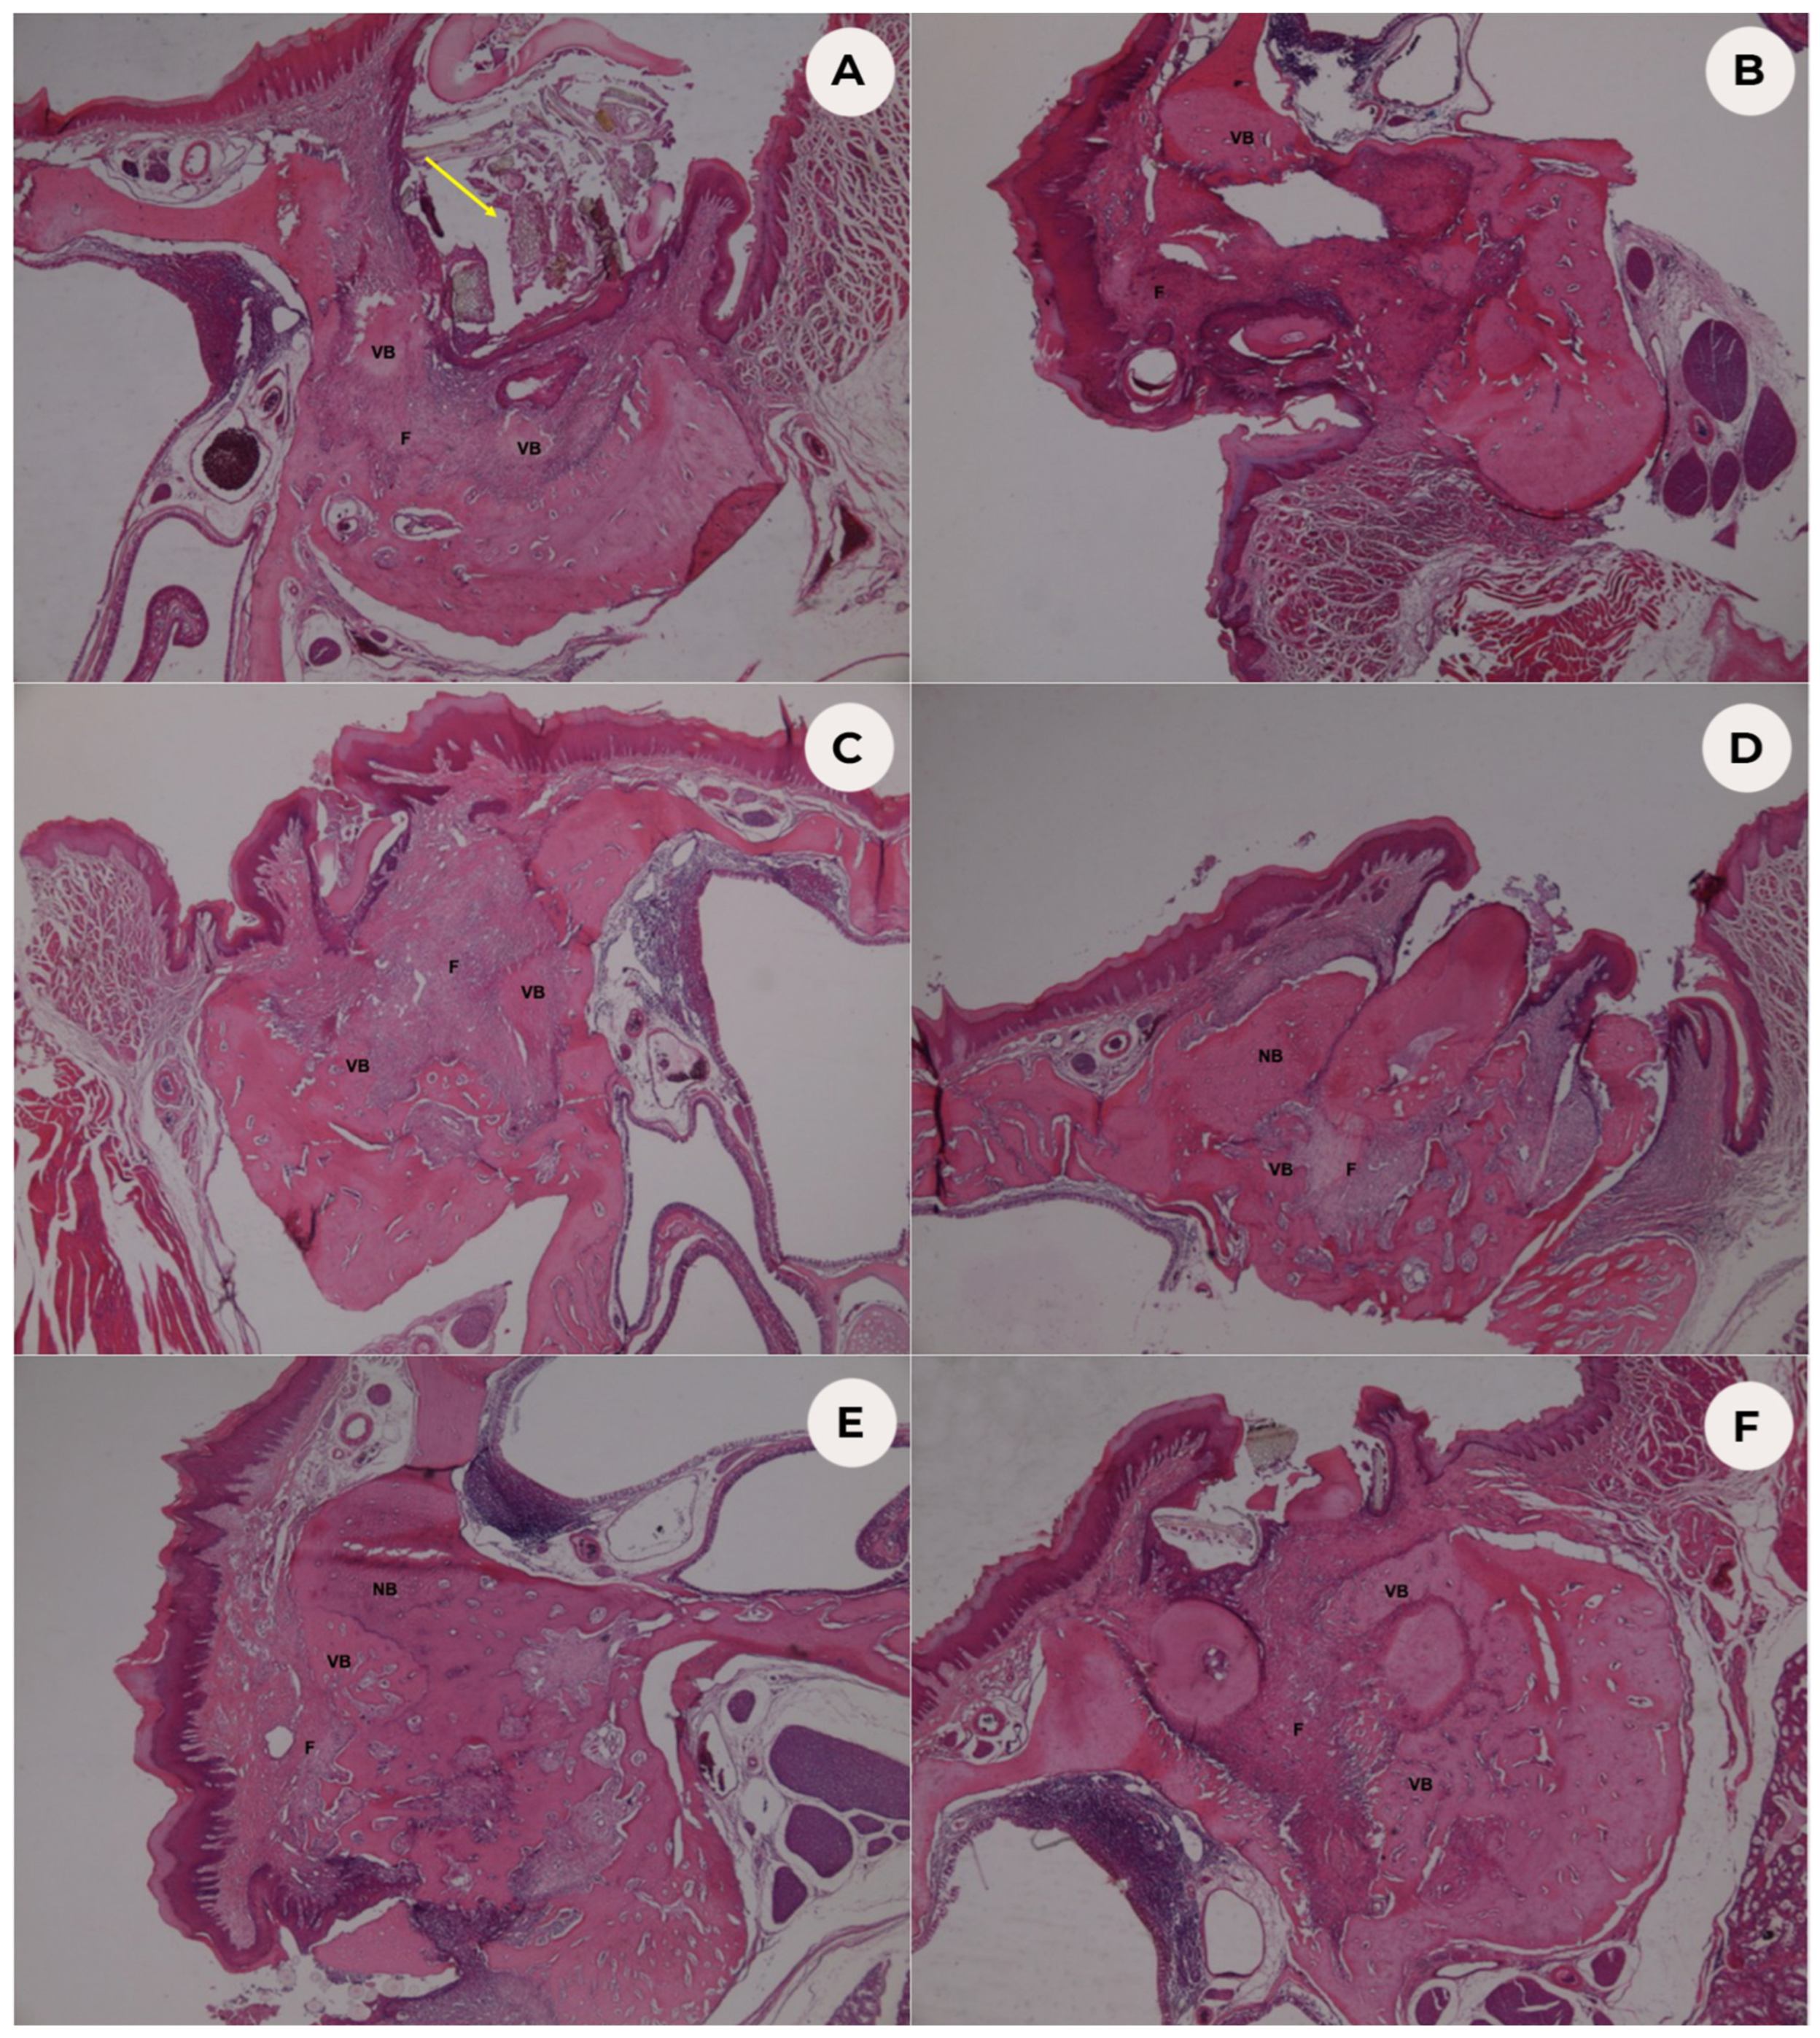

3.1. Histopathological Analysis

3.2. Histomorphometric Analysis